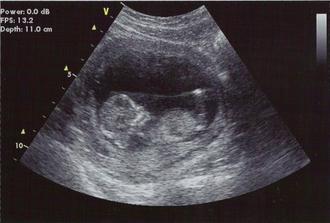

17.2.2009velký morfo ultrazvuk v Gennetu - vše v nejlepším pořádku HURÁ :o) pan doktor všechno přeměřil a ukázal nám všechno co šlo včetně ledvin, plného močového měchýře :o), nožiček a ručiček s prstíčkama :o) a krásně pracujícího srdíčka - máme 480g no prostě nádhera. A nakonec nám svěřil to velké tajemství......v bříšku se nám schovává malá princeznička :o))